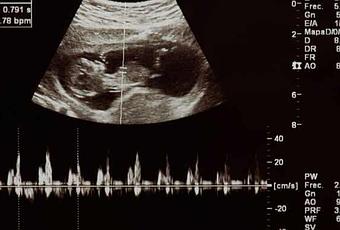

Ha levantado revuelo el anuncio en Castilla-León de la oferta obligada de escuchar el latido fetal, ver una ecografía y atención psicológica antes del aborto. Se le ha replicado que una intervención médica debe tener siempre información para poder tomar una decisión verdaderamente libre. No obstante, este argumento no hace mella: lo que se pretende al no informar es una libertad sin ataduras, ni siquiera las derivadas de un conocimiento mínimo de la realidad.